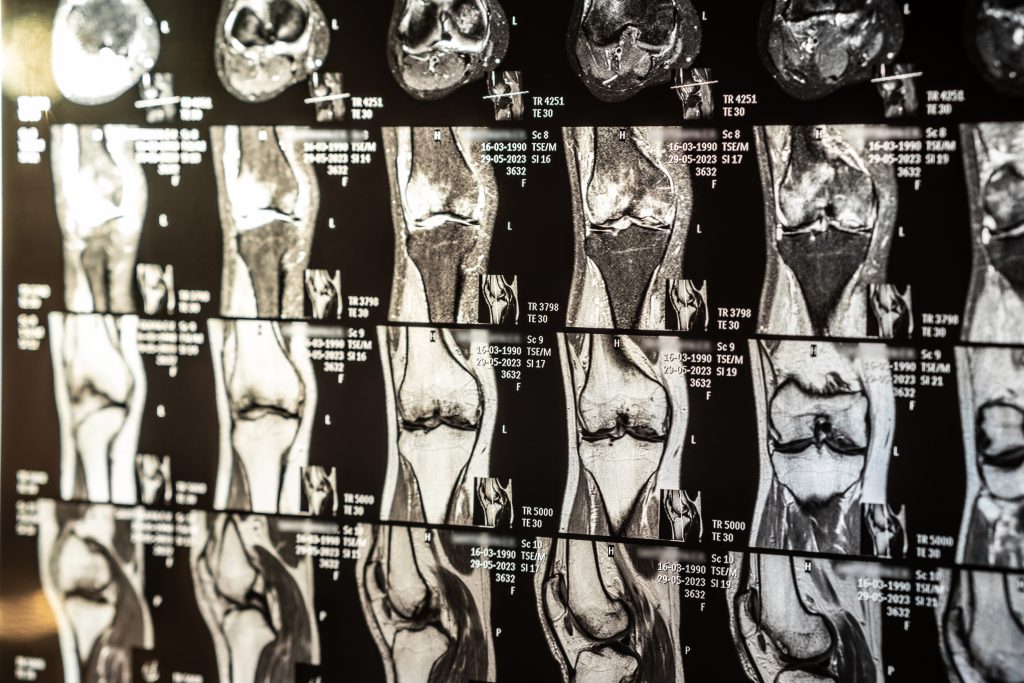

A ressonância magnética é uma das principais ferramentas da medicina esportiva, sendo essencial para a avaliação de atletas profissionais e amadores.

O exame ajuda a identificar lesões por esforço repetitivo, inflamações e desgastes articulares, que podem comprometer o desempenho esportivo. Com um diagnóstico preciso, médicos e fisioterapeutas podem planejar tratamentos eficazes e garantir uma recuperação mais segura.

Antes de cirurgias ortopédicas, a ressonância magnética fornece imagens detalhadas das estruturas afetadas, permitindo que o médico escolha a melhor abordagem cirúrgica.

No pós-operatório, a ressonância magnética é utilizada para monitorar a recuperação, garantindo que o tratamento esteja evoluindo conforme o esperado.